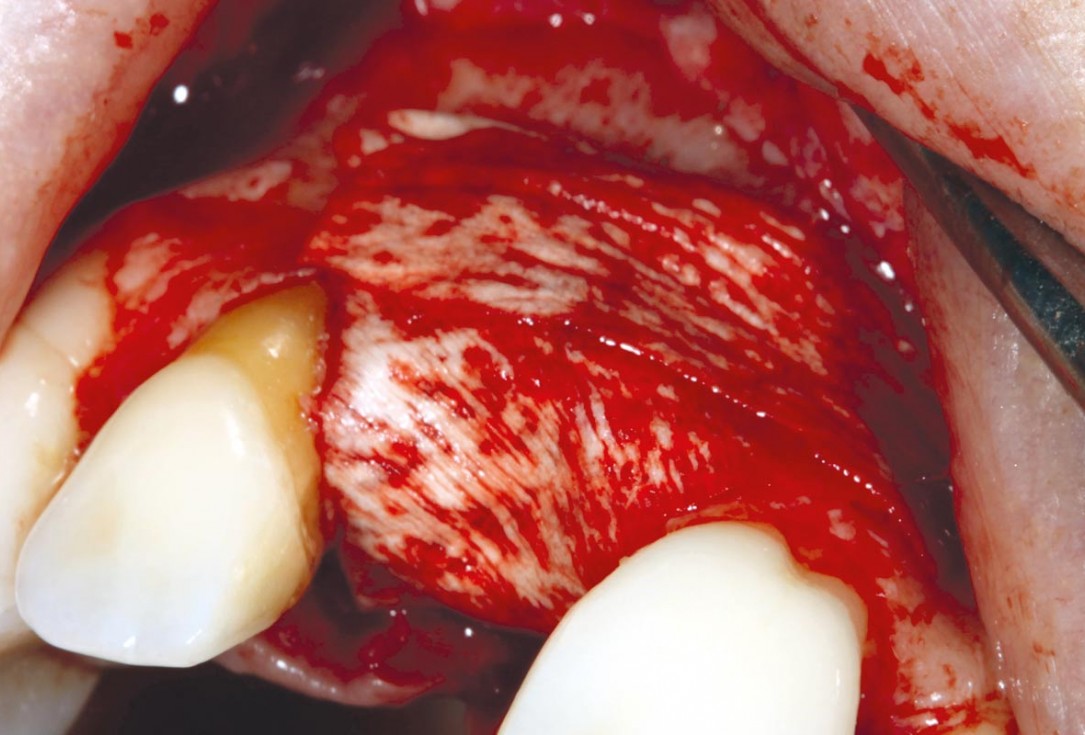

3/11 - Fixation of cortico facially and palatallymaxgraft® cortico at combined defect palatally and facially - Dr. K. Höckl

4/11 - Removal of sharp edgesmaxgraft® cortico at combined defect palatally and facially - Dr. K. Höckl